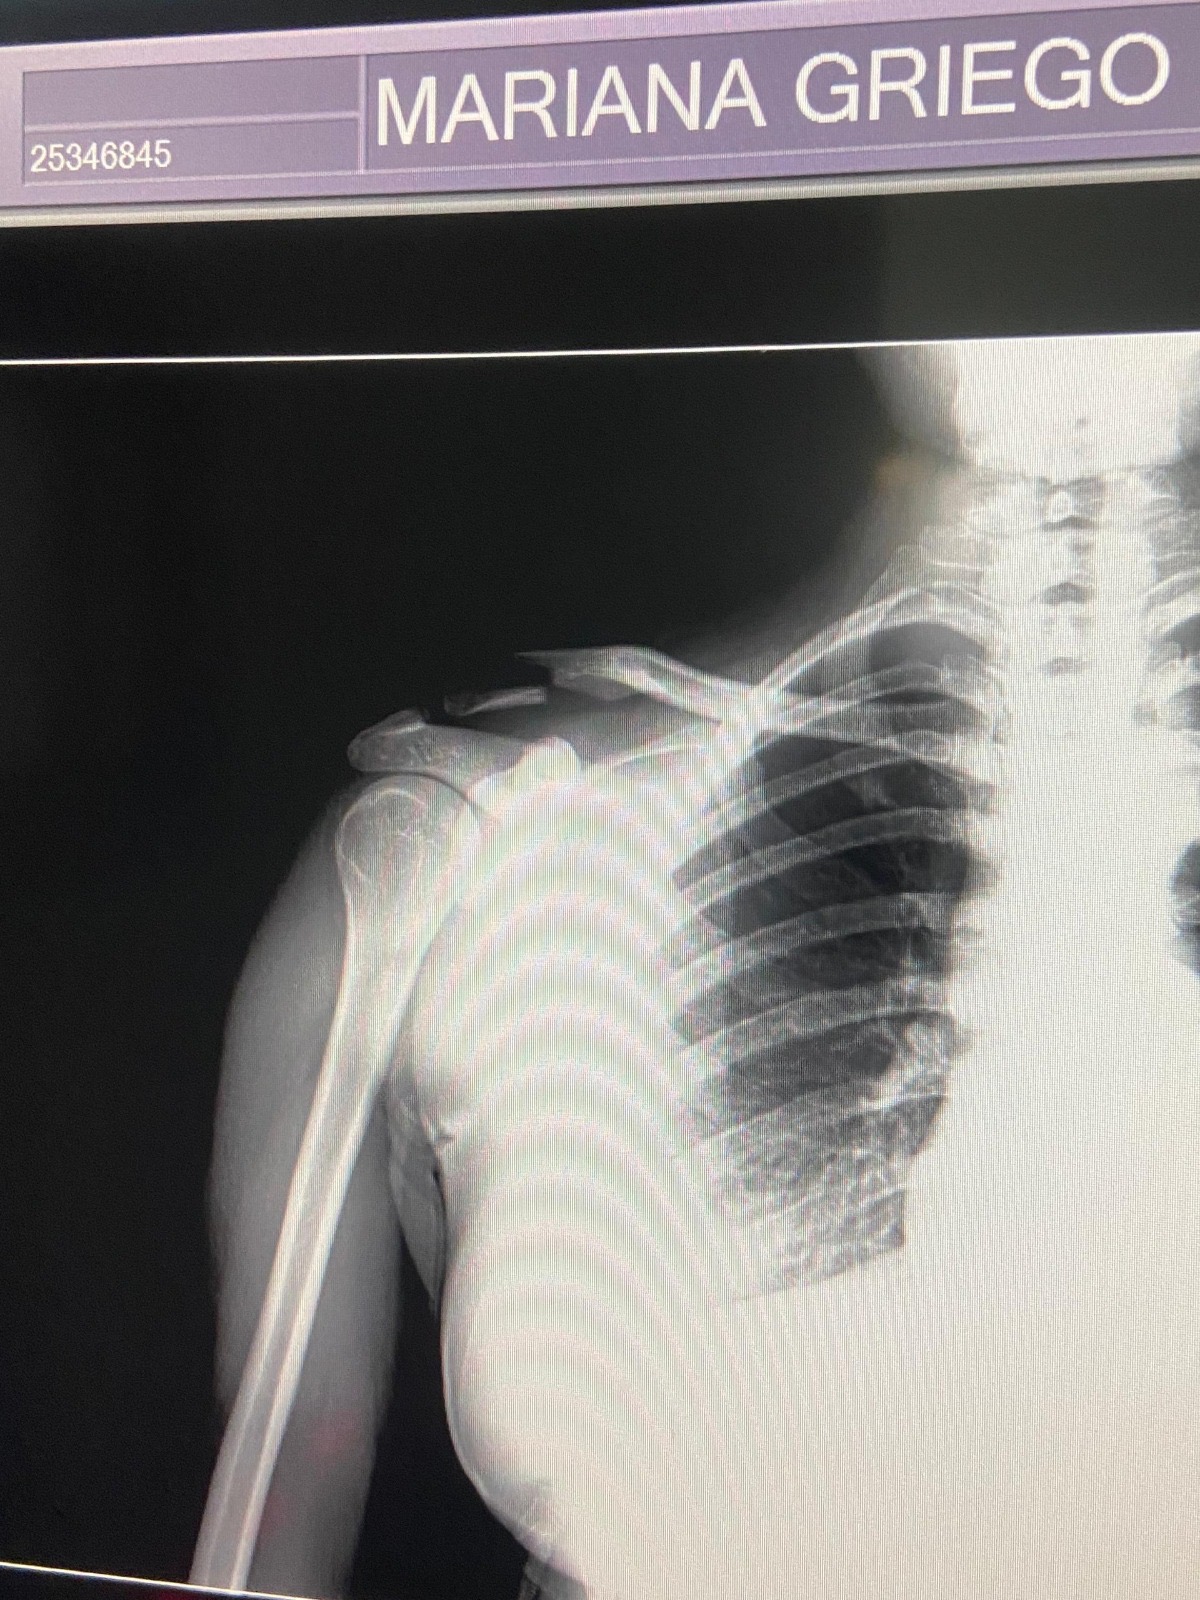

El impacto me ocasionó una fractura de clavícula lateral desplazada, una lesión dolorosa que me impide moverme y realizar mis actividades básicas. La única forma de recuperar la funcionalidad de mi brazo y llevar el hueso a su lugar original es a través de una cirugía para colocar una placa. Lamentablemente, los costos quirúrgicos, los insumos, los tratamientos postoperatorios y la rehabilitación posterior superan por completo mis posibilidades económicas en este momento. Como persona trabajadora y de mucha fe, lo que más deseo es recuperar mi salud para volver a mi rutina, ser productiva nuevamente y seguir dedicándome a mi profesión, que disfruto tanto, así como a mi familia. Pero hoy me toca hacer una pausa y pedir una mano amiga.